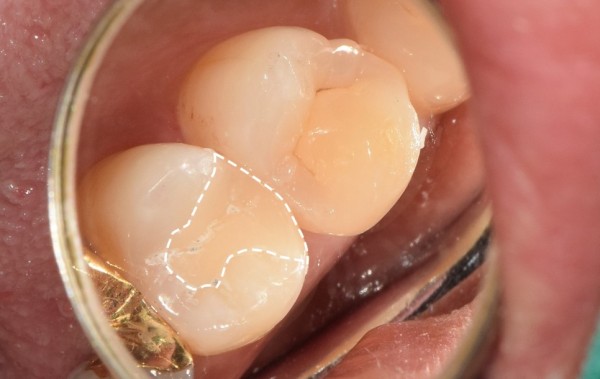

치아와 비슷한 세라믹 인레이로 제작하여 치료가 끝난 모습입니다.

위처럼 표시를 안했다면 어디를 치료했는지 잘 모르실 수 있습니다.

심미적으로도 좋고, 세라믹 재료의 인레이는 높은 경도를 가지고 있어

파절될 위험도 많이 낮답니다.